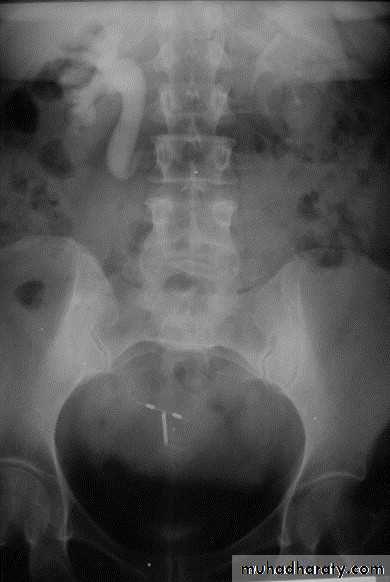

22- PUJ obstruction23- horse shoe24- PUJ obstruction25- double ureter26- partial PUJ obstruction27- double ureter28- schistosoma of bladder29- filling defect in the pelvi-calycial system30- tumor 31- filling defect (stone)